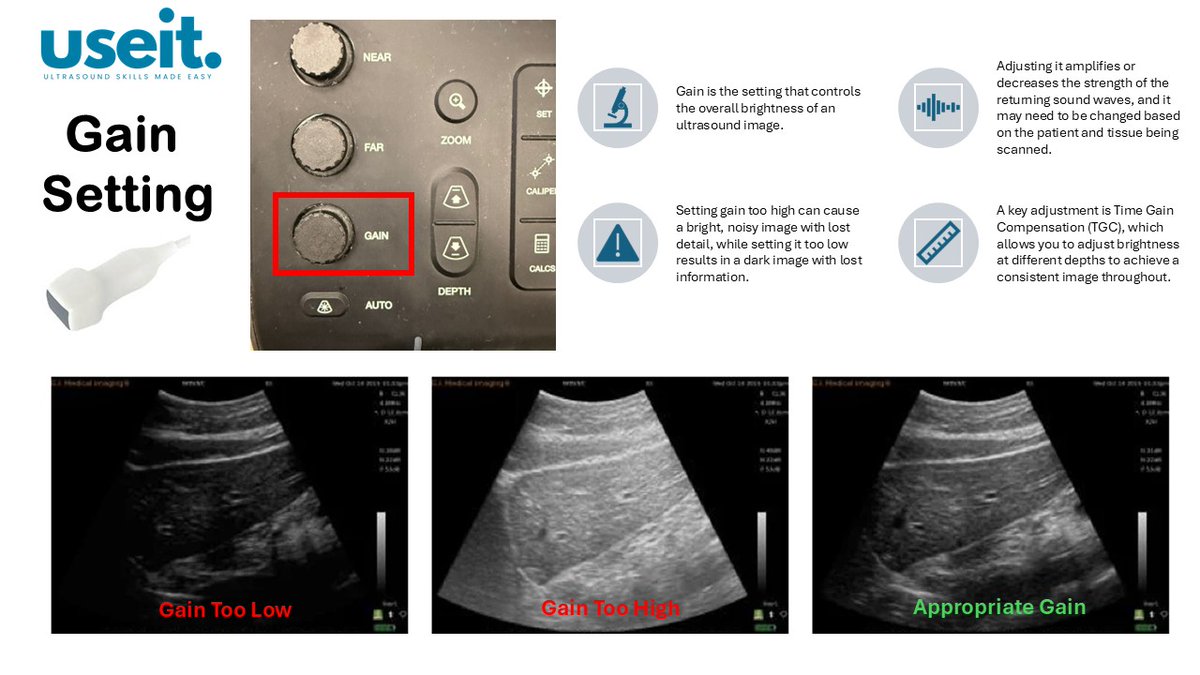

#useit #POCUS Gain Setting & TGC. Basic ultrasound knobology to optimise your images. Image Source: eimedical.com/blog/understan…

pocus_today's tweet image. #useit #POCUS  Gain Setting & TGC. Basic ultrasound knobology to optimise your images.

Image Source: eimedical.com/blog/understan…